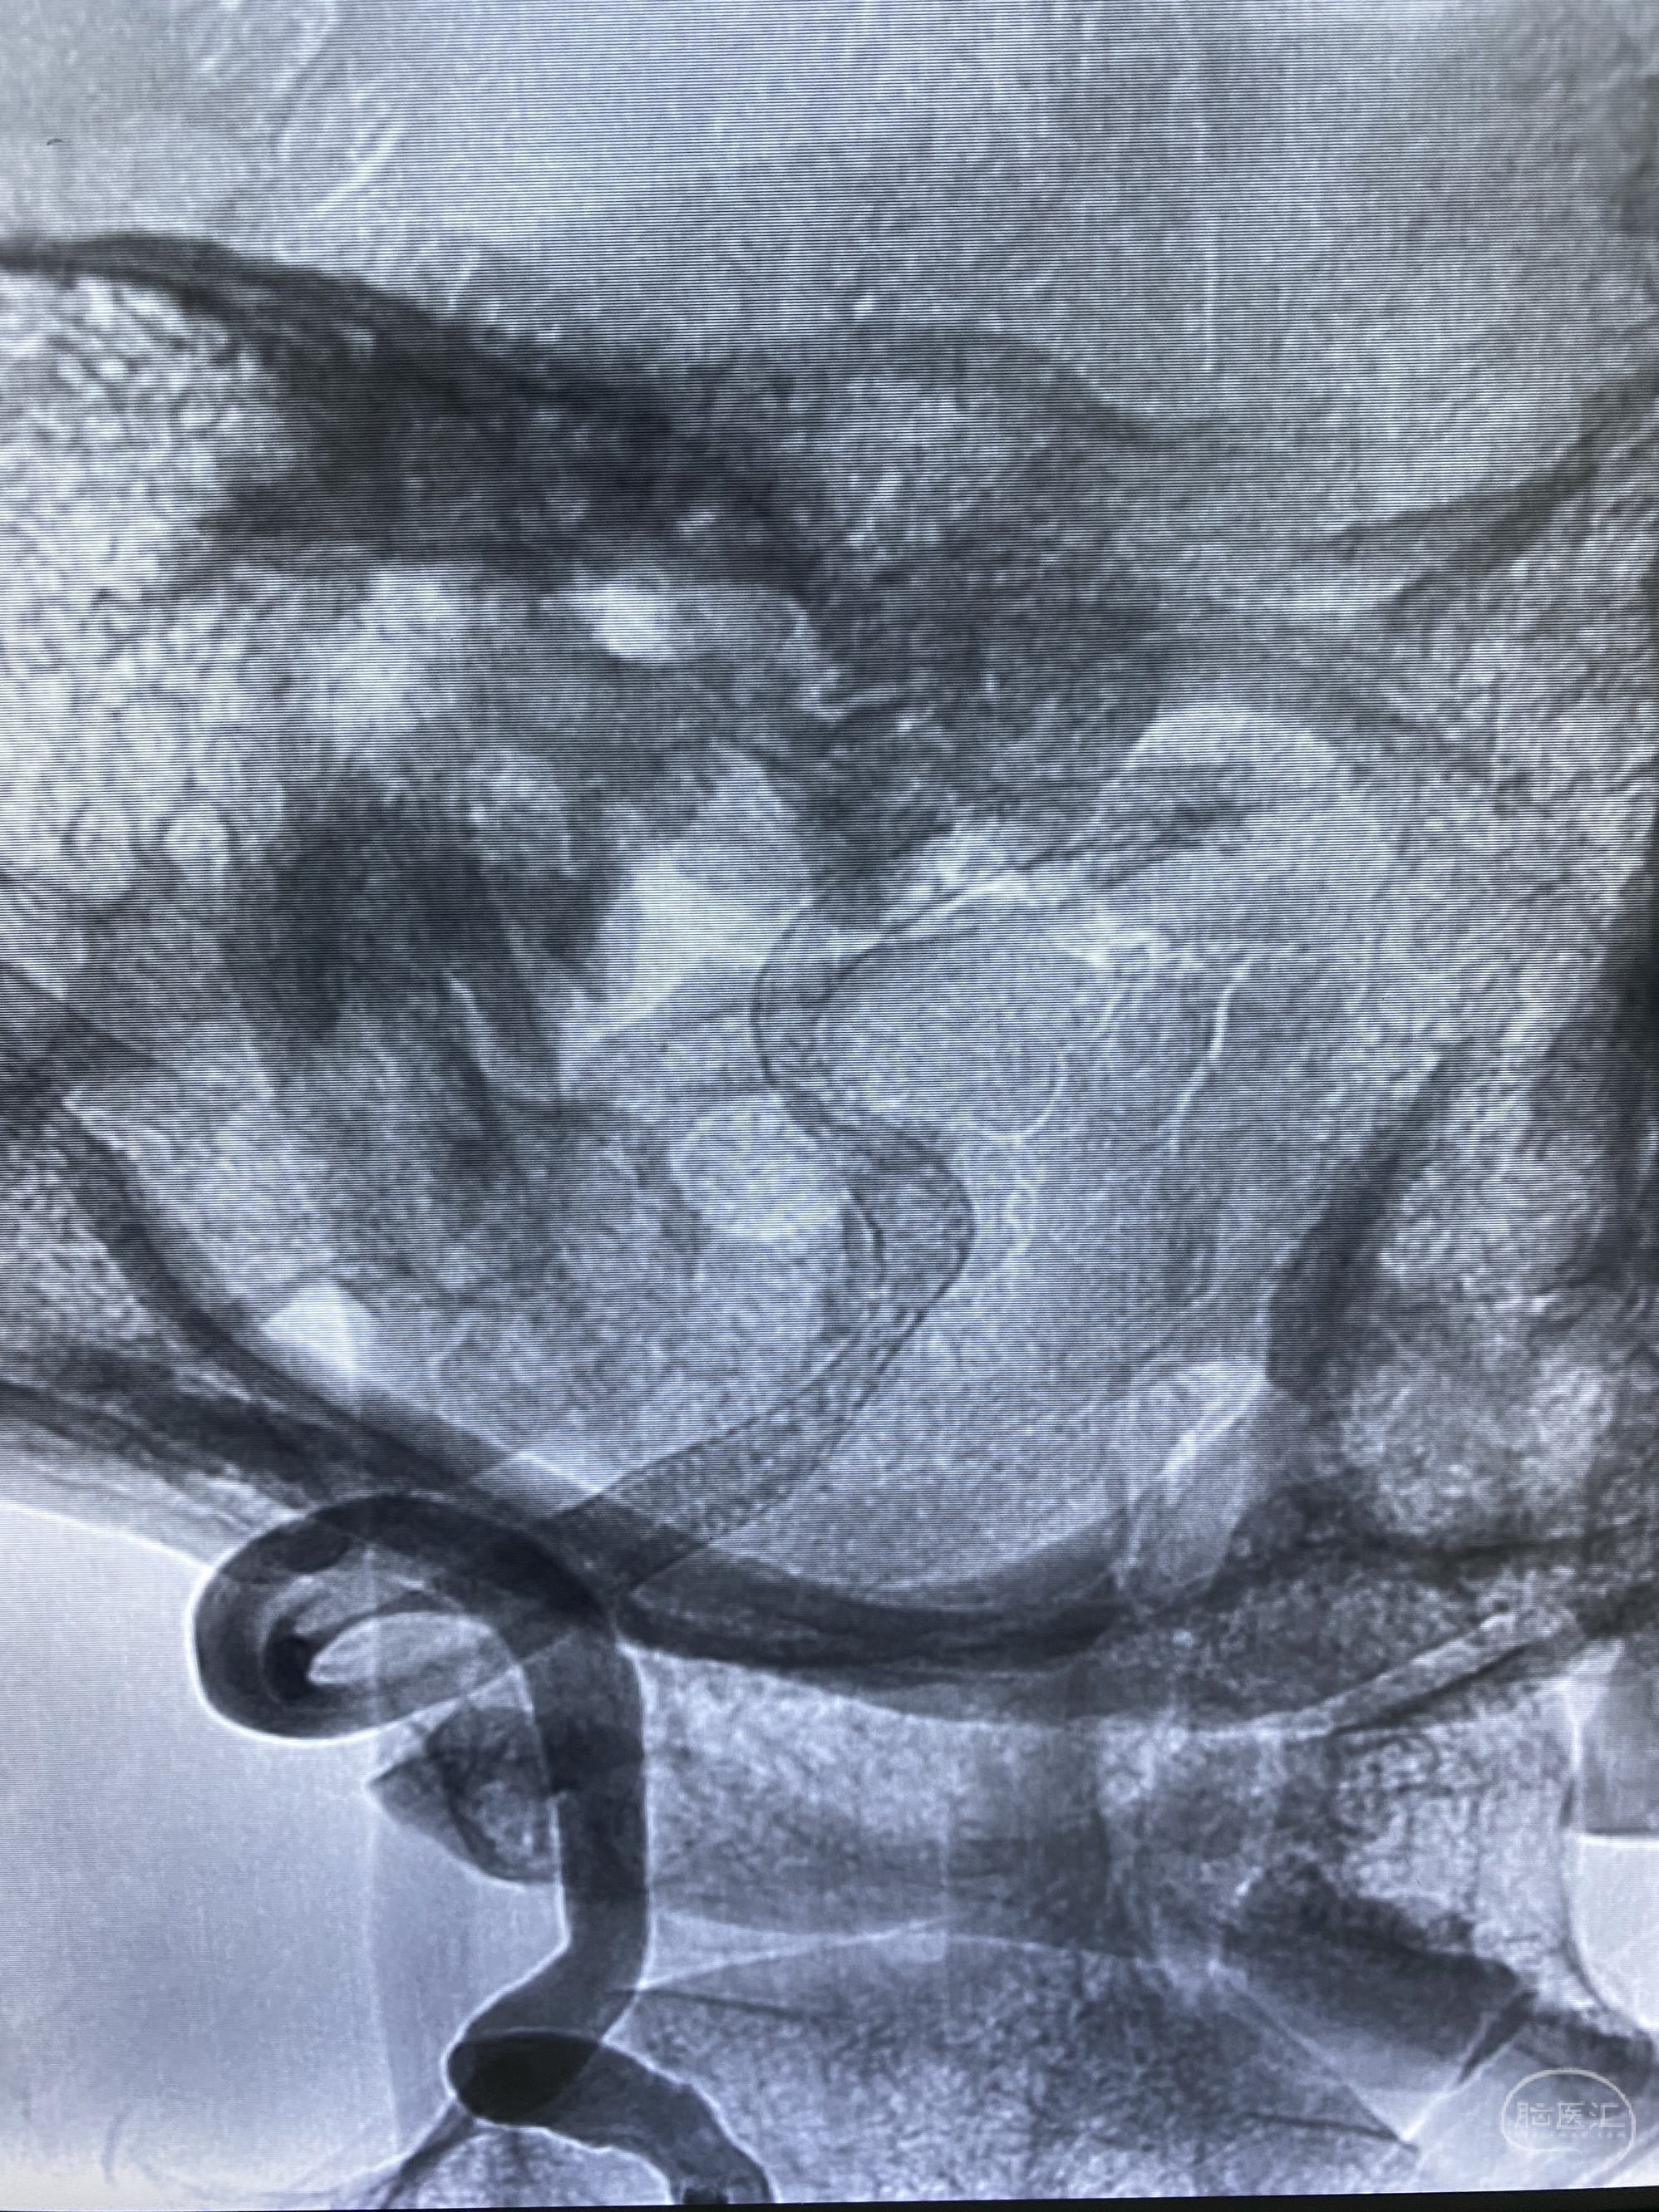

今日手术,TJG,M62Y,一期左侧颈动脉狭窄支架植入,二期椎动脉V4段多发夹层动脉瘤伴狭窄,常规支架辅助栓塞方法复杂又危险,血流导向装置植入快捷又安全。南阳市中心医院神经内科脑血管病介入团队pipeline flexFD植入两人导师资格。

椎动脉颅内段多发夹层动脉瘤伴载瘤动脉狭窄pipeline flex植入

今日手术,TJG,M62Y,一期左侧颈动脉狭窄支架植入,二期椎动脉V4段多发夹层动脉瘤伴狭窄,常规支架辅助栓塞方法复杂又危险,血流导向装置植入快捷又安全。南阳市中心医院神经内科脑血管病介入团队pipeline flexFD植入两人导师资格。